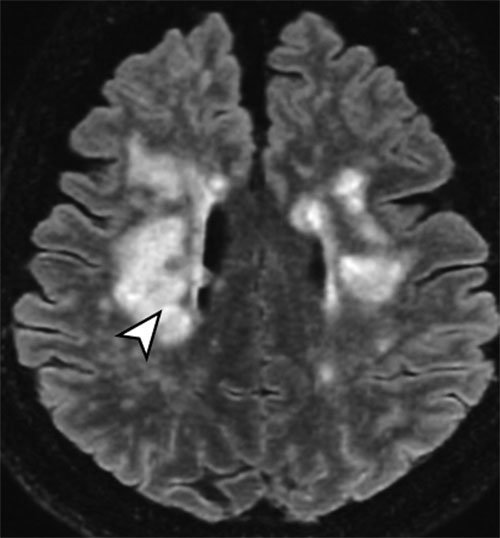

코로나19 완치 후 섬망을 겪던 환자의 뇌를 자기공명영상(MRI) 장치로 촬영한 모습. 미세 출혈이 발생한 곳이 화살표로 표시돼 있다. 프랑스 파리뇌연구소 연구팀 제공

15일(현지 시간) 프랑스 파리뇌연구소 연구팀은 신종 코로나바이러스 감염증(코로나19)에 감염됐다가 완치된 57명의 뇌를 자기공명영상(MRI)으로 찍은 모습을 공개했다. 영상 분석 결과 57명 가운데 41명의 뇌에서 괴사 증상이 일어나는 허혈성 병변과 관류 이상, 미세 출혈 흔적이 나타났다. 코로나19가 뇌를 공격한 흔적이다.